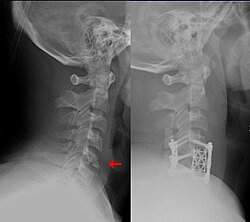

정형외과 의사와 신경외과 의사 가 치료하는 질환 중 하나인 하부 경추 골절

2006년 9월에 촬영된 이 사진은 2000년에 시행된 오른쪽 비구(acetabulum )의 대대적인 수리 작업 6년 후의 모습을 보여줍니다. 뼈/관절 질환인 관절염이 발병하면서 관절 손상이 더욱 뚜렷해졌습니다.